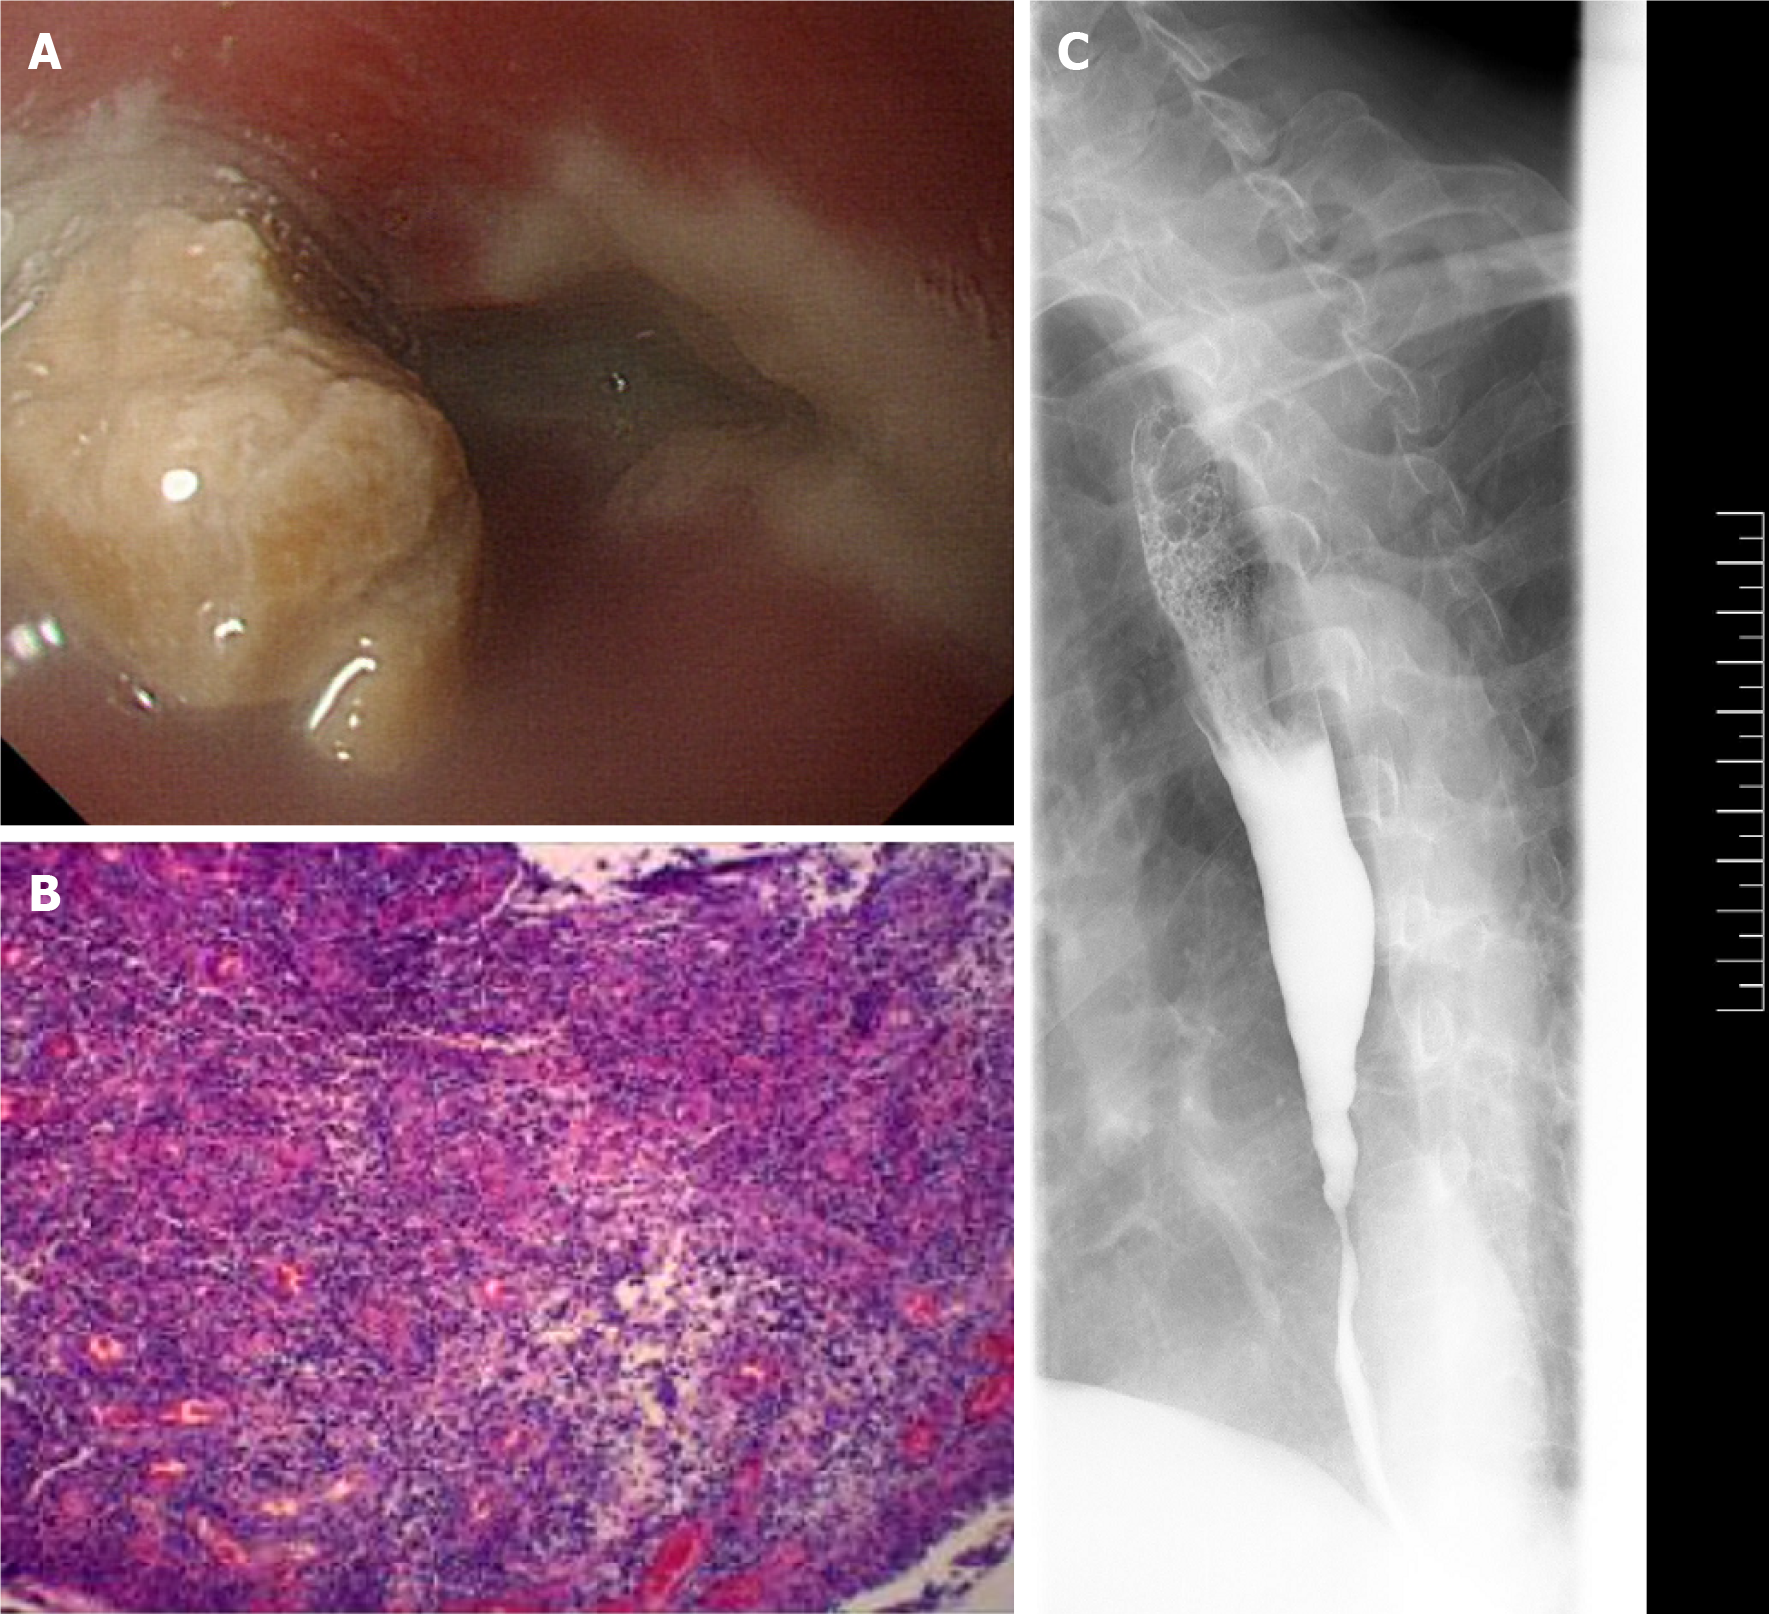

Figure 2 Preoperative tests prior to stent placement for post-inflammatory oesophageal strictures in a 68-year-old man.

A: The endoscopic examination revealed an oesophageal stricture 35 cm from the incisors, with food obstructing the esophagus and preventing endoscopic passage; B: The oesophagogram revealed a 4.7 cm severe stricture in the lower esophagus; C: The pathology showed chronic inflammation of oesophageal mucosa with ulcer and inflammatory granulation tissue hyperplasia.